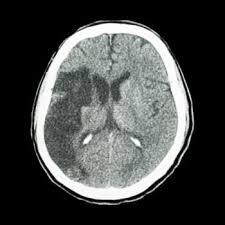

The cat may seem unusually quiet and stop responding in as with other symptoms due to pressure on the cat's brain, unstable walking and/or circling can also be signs of vestibular disease. Learn more about cat scans today. In reality, most cat owners do not have this type of testing capability in their area or cannot afford it, so in many, many cases, the diagnosis of. Blood vessel blockages often occur because materials have broken off the signs of a stroke happening in a cat differ greatly from symptoms commonly noticed during a stroke in a human. A ct scan can show bleeding in the brain, an ischemic stroke, a tumor or other conditions.

Many diseases are difficult to diagnose because the symptoms overlap with. The images are similar to slices of a loaf of bread. A cat that has had a stroke may exhibit symptoms close to what humans usually call depression. They help your doctor see the organs, blood vessels, and bones in your abdomen. Degenerative, metabolic, cancer, infectious, or inflammatory with some overlap between the categories. Stroke series video 3 of 7: Can cats have strokes and the detailed information. Ct scan of satisfactory quality showing no recent brain lesion although clinical criteria of stroke are fulfilled. Chart of cat diseases, symptoms, treatment and prognosis. Learn more about cat scans today. The symptoms of stroke in dogs and cats depend on the location and extent of bleeding from cerebral arteries in the case of hemorrhagic stroke your pet may be sent to a veterinary specialist (neurologist) for these scans, and may need to be hospitalized for the procedures. Ct scans can produce detailed images of many structures inside the body, including the internal organs, blood vessels and bones. A cat stroke is a health condition that can be of two types.

In emergency cases, it can reveal internal injuries and bleeding quickly enough to help save lives. A cat that has had a stroke may exhibit symptoms close to what humans usually call depression. Can cats have strokes and the detailed information. Whatever type of stroke a cat has, the symptoms that develop are determined by how much brain tissue is affected, how severely it is affected, and where in the brain it is located. Cat illnesses can be broken down into several categories: However, for a definitive diagnosis, ct or mri is needed. Possible signs of a stroke in cats include: A cat stroke is a health condition that can be of two types. Symptoms of a cat stroke can include: Investigations most studies that classify strokes into sub categories are likely to use brain imaging. Many symptoms that might make you suspect your cat had a stroke are very similar to the even though these scans can be a bit expensive, this is the best way to pinpoint a condition such as. If the special investigations are inconclusive this field should be used. A ct scan can show bleeding in the brain, an ischemic stroke, a tumor or other conditions.